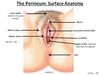

What parts of the female reproductive tract are in the perineum?

inferior vagina

Perineal muscles

Bartholin’s glands

Clitrois

Labia

what nerve supplies the perineal muscles?

Pudendeal nerve

What is the perineal body?

bundle of collangenous elastic tissue which the perineal muscles attatch too

What do you call the little anchor point the perineal muscles attatch too?

The perineal body

Where are the bartholins glands?